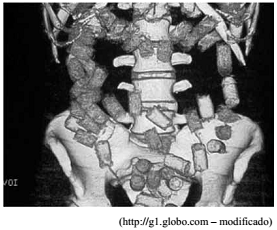

“Traficante é preso em aeroporto com cápsulas de cocaína no estômago. Ele foi detido no Aeroporto de Foz do Iguaçu tentando embarcar para a Espanha. A droga estava dividida em 74 cápsulas, conforme ilustra a figura, as quais foram expelidas em hospital.”

Tendo em vista a fisiologia e a anatomia do sistema digestório humano, assinale a alternativa que apresenta um erro conceitual cometido na redação da notícia.